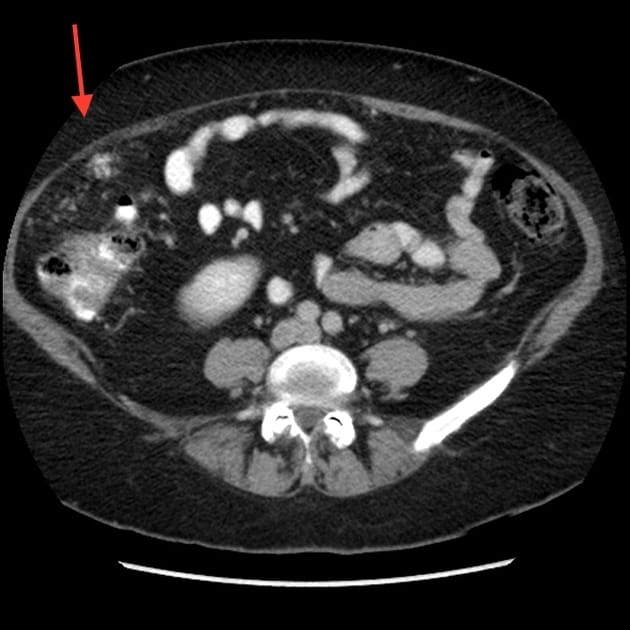

Di căn phúc mạc

Di căn phúc mạc - Ảnh 3

» Thông tin: Nữ giới – 60 tuổi.

» Lâm sàng: Đau mạn sườn phải / Tiền sử buồng trứng.